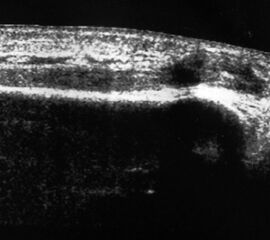

Fibulaverletzung beim Erwachsenen

Fibulafraktur mit Unterbrechung der Kortikalis und Hämatom.

Abbildung 13

Lagerung: Rückenlage, leichte Innrotation des Fußes.

Schnittebene: LS über distaler Fibula.

Referenzstruktur: Fibula im Längsverlauf.

Befunde: Bei einer Außenknöchelfraktur ist eine Unterbrechung der echogenen metaphysären Knochenlinie mit umgebendem flachen, echoarmen periostalen Hämatom zu sehen (Abb.13).

Cave: Ein Os subfibulare kann ebenfalls fälschlicherweise als Fibulaverletzung interpretiert werden!